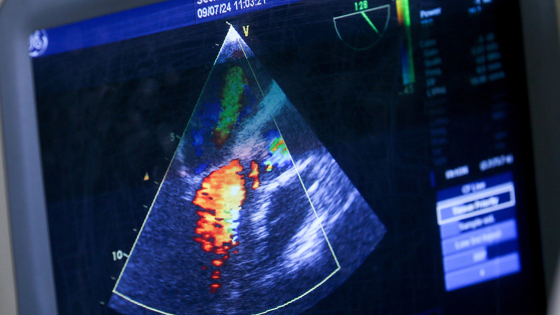

Как рассказала член-корреспондент РАН Нана Погосова, в последние два-три года зафиксирована самая низкая за последние 30 лет смертность от сердечно-сосудистых заболеваний: «Мы активно внедряли высокотехнологичную медицинскую помощь, например, в 2024 году было проведено больше 300 тысяч коронарных стентирований. Это позволило снизить больничную смертность от сосудистых катастроф на 25%. Но от хронических форм ССЗ люди по-прежнему умирают и становятся инвалидами».